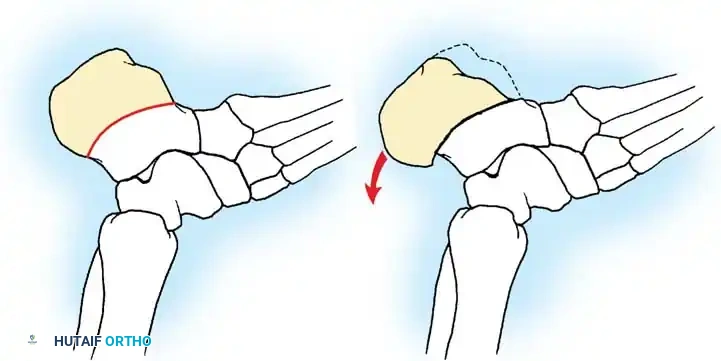

## فهم طبيعة المشكلة وكيفية حدوثها لفهم كيفية حدوث تشوهات القدم في الشلل الدماغي، يجب أن ننظر إلى العلاقة المعقدة بين الأعصاب والعضلات والعظام. في الحالة الطبيعية، تعمل العضلات في أزواج متوازنة (عضلات تشد وأخرى ترخي) لتوجيه حركة المفصل. ولكن في حالة الشلل الدماغي، ترسل الإشارات العصبية غير المنتظمة أوامر مستمرة لبعض العضلات بالانقباض (التشنج)، مما يخلق قوى غير طبيعية وغير متكافئة على عظام ومفاصل القدم. النوع الأكثر شيوعاً من هذه التشوهات هو "القدم الخيلية" أو المشي على أطراف الأصابع، حيث تكون القدم مشدودة لأسفل. وتحدث تشوهات أخرى مثل انحراف القدم للداخل أو انحراف القدم للخارج بنسب متقاربة، وذلك يعتمد بشكل كبير على التوزيع التشريحي للإصابة العصبية لدى الطفل. وقد أثبتت الدراسات الكبرى أن وجود تشوه في القدم، خاصة إذا كان في كلتا القدمين، يؤثر بشكل سلبي وكبير على قدرة الطفل على المشي ويزيد من المجهود البدني المطلوب للحركة مقارنة بالأطفال الذين يعانون من إصابة في قدم واحدة.  ## أسباب وعوامل تطور تشوهات القدم من المهم جداً للآباء أن يدركوا أن تشوهات القدم في الشلل الدماغي نادراً ما تكون ثابتة؛ بل هي تتطور وتتغير ديناميكياً بمرور الوقت، وتحديداً خلال فترات النمو السريع لهيكل الطفل العظمي. تكمن المشكلة الأساسية في أن العظام تنمو بمعدل طبيعي، بينما العضلات المتشنجة والمشدودة (مثل عضلة الساق الخلفية) لا تنمو بنفس السرعة وتفتقر إلى المرونة اللازمة لمواكبة نمو العظام. هذا التفاوت يؤدي إلى قصر نسبي في العضلة والوتر، مما يسحب القدم إلى وضعيات غير طبيعية. على سبيل المثال، قد يبدأ الطفل الصغير بتشوه مرن في القدم، ولكن مع استمرار التشنج العضلي وقوى الشد غير الطبيعية أثناء المشي، قد يتحول هذا التشوه المرن بمرور الوقت إلى تشوه عظمي صلب وتيبس كامل في المفصل. بالإضافة إلى ذلك، فإن تشنج العضلات الدقيقة داخل القدم يمكن أن يؤدي إلى تشوهات ثانوية في الأصابع ومقدمة القدم، مثل انحراف إصبع القدم الأكبر أو التصاق الأصابع. ## الأعراض والعلامات التحذيرية التشوه الأبرز والأكثر شيوعاً هو "القدم الخيلية"، والذي يصيب ما يصل إلى 70% من الأطفال المصابين. وهناك علامات يجب على الآباء الانتباه لها: * المشي المستمر على أطراف الأصابع وعدم القدرة على ملامسة الكعب للأرض. * رجوع الركبة للخلف بشدة أثناء الوقوف أو المشي للتعويض عن قصر وتر أخيل. * صعوبة بالغة في إدخال قدم الطفل في الحذاء العادي. * تآكل الحذاء بشكل غير متساوٍ من جهة معينة. * ألم في القدم أو الساق بعد المشي لمسافات قصيرة. * ظهور تقرحات جلدية في مناطق الضغط غير الطبيعي، خاصة لدى الأطفال الذين يستخدمون الكراسي المتحركة. ## التقييم الطبي والتشخيص يبدأ التقييم الطبي الدقيق بزيارة طبيب جراحة عظام الأطفال المتخصص. سيقوم الطبيب بإجراء فحص سريري شامل لتقييم: * مدى التشنج العضلي في الساق والقدم. * الفرق بين التشوه المرن الذي يمكن تصحيحه باليد، والتشوه الصلب (الثابت). * تحليل نمط مشي الطفل. * إجراء اختبارات خاصة مثل اختبار سيلفرسكيولد لتحديد ما إذا كان الشد ناتجاً عن عضلة الساق العلوية فقط أم يمتد ليشمل وتر أخيل بالكامل. ## الخيارات العلاجية غير الجراحية يعتبر العلاج التحفظي (غير الجراحي) هو خط الدفاع الأول، والهدف الأساسي منه هو الحفاظ على مرونة المفاصل، وتحسين وظيفة القدم، وتأخير الحاجة للتدخل الجراحي قدر الإمكان حتى يكبر الطفل، مما يقلل من احتمالية عودة التشوه. تشمل الخيارات غير الجراحية ما يلي: ### العلاج الطبيعي المكثف يركز العلاج الطبيعي على تمارين الإطالة السلبية للعضلات المتشنجة. وقد أثبتت الأبحاث أن العضلة تحتاج إلى فترات طويلة من الإطالة اليومية لمنع حدوث قصر دائم فيها، وهو ما يتطلب التزاماً كبيراً من الأسرة. ### استخدام الجبائر والأجهزة التعويضية تعتبر الجبائر البلاستيكية الداعمة للكاحل والقدم من أهم أدوات العلاج. وتستخدم الجبائر الليلية الصلبة بشكل خاص للحفاظ على القدم في وضع معتدل ولمواجهة التشنجات التي تزيد أثناء النوم. ### الحقن والجبس المتسلسل يُعد حقن البوتكس في العضلات المتشنجة إجراءً فعالاً لإرخاء العضلة مؤقتاً. وغالباً ما يُتبع الحقن بوضع سلسلة من قوالب الجبس التي يتم تغييرها كل أسبوعين إلى ثلاثة أسابيع لإطالة العضلة تدريجياً وتحسين المدى الحركي للمفصل.  | نوع العلاج التحفظي | الهدف الرئيسي | ملاحظات هامة | | :--- | :--- | :--- | | العلاج الطبيعي | الحفاظ على مرونة العضلات والمفاصل | يحتاج إلى استمرارية والتزام يومي | | الجبائر التقويمية | منع تفاقم التشوه وتثبيت القدم | ضرورية جداً أثناء فترات النوم | | حقن البوتكس | إرخاء العضلات المتشنجة مؤقتاً | تأثيره يستمر لعدة أشهر ويساعد في تأخير الجراحة | | الجبس المتسلسل | إطالة الأوتار تدريجياً | يستخدم غالباً بالتزامن مع حقن البوتكس | ## دواعي التدخل الجراحي لتشوهات القدم يصبح التدخل الجراحي ضرورياً عندما تفشل الطرق التحفظية في السيطرة على التشوه، أو عندما يصبح التشوه ثابتاً ويعيق حياة الطفل. تختلف دواعي الجراحة بناءً على قدرة الطفل على المشي: **للأطفال القادرين على المشي:** يتم اللجوء للجراحة عند عدم قدرة الطفل على وضع كاحله في زاوية قائمة أثناء المشي مع فرد الركبة، مما يؤدي إلى المشي على أطراف الأصابع، أو التواء الركبة للخلف، أو رفع الكعب مبكراً أثناء المشي. **للأطفال غير القادرين على المشي:** تُجرى الجراحة لتخفيف التقلصات الشديدة التي تمنع ارتداء الأحذية، أو تعيق برامج الوقوف المدعوم، أو تتسبب في تقرحات جلدية وصعوبات في النظافة الشخصية. > **تحذير جراحي بالغ الأهمية خطر الإطالة المفرطة** > يجب على الجراح توخي الحذر الشديد لتجنب الإطالة المفرطة لوتر أخيل أو عضلة الساق، خاصة لدى الأطفال الذين يمشون. الإطالة الزائدة تدمر القوة الدافعة للقدم وتؤدي إلى تطور ما يُعرف بـ "مشي القرفصاء". هذا النمط من المشي كارثي من الناحية الميكانيكية، حيث يؤدي إلى إرهاق سريع لعضلات الفخذ الأمامية وفقدان القدرة على المشي المستقل.  ## عمليات تطويل وتر أخيل نظراً لاختلاف حالات الشلل الدماغي، توجد تقنيات جراحية متعددة لتصحيح تشوه القدم الخيلية. تعتمد نسبة نجاح العملية وعدم عودة التشوه بشكل كبير على عمر الطفل وقت الجراحة ونوع الشلل الدماغي. تشير الدراسات إلى أن إجراء الجراحة بعد سن السادسة يقلل بشكل كبير من احتمالية عودة التشوه مقارنة بإجرائها في سن مبكرة جداً. يمكن إطالة مجمع عضلة الساق ووتر أخيل في مستويين رئيسيين: إما عند اتصال العضلة بالوتر، أو في وتر أخيل نفسه. ### التطويل المفتوح لوتر أخيل تُستخدم هذه التقنية (وتعرف بتعديل وايت) وتعتمد على الانزلاق الطبيعي لألياف وتر أخيل التي تلتف حول نفسها بطبيعتها التشريحية.  **خطوات العملية الجراحية:** * يتم عمل شق جراحي طولي خلف الكاحل للوصول إلى الوتر. * يقوم الجراح بعمل قطع جزئي في الجزء السفلي من الوتر، وقطع جزئي آخر في الجزء العلوي في اتجاه معاكس. * عندما يتم دفع القدم بلطف إلى الأعلى (نحو الساق)، تنزلق ألياف الوتر المقطوعة فوق بعضها البعض، مما يؤدي إلى زيادة طول الوتر للمستوى المطلوب لتصحيح التشوه. * تتميز هذه الطريقة بالحفاظ على الغلاف المحيط بالوتر لمنع الالتصاقات.   بعد العملية، يتم وضع قدم الطفل في جبس قصير يمتد تحت الركبة لمدة 4 أسابيع، ويُسمح للطفل بالمشي عليه. بعد إزالة الجبس، يتم استخدام جبيرة بلاستيكية مخصصة للحفاظ على النتيجة. ### التطويل على شكل حرف زد توفر هذه التقنية تحكماً دقيقاً للغاية في مقدار الإطالة المطلوبة، مما يجعلها الخيار الأمثل للتقلصات الشديدة والصلبة.  **كيف تتم العملية؟** * يتم شق الوتر طولياً في المنتصف، ثم يتم قطع نصف الوتر من الأسفل والنصف الآخر من الأعلى، مما يشكل حرف Z. * يتم سحب الأطراف لزيادة الطول بدقة متناهية، ثم يتم خياطة الأطراف معاً باستخدام خيوط جراحية قوية. * يتم ضبط درجة شد الوتر بناءً على شدة التشنج العضلي لدى الطفل لضمان أفضل نتيجة وظيفية.      يتطلب هذا الإجراء وضع جبس لمدة 6 أسابيع، يليه استخدام الجبائر الداعمة بشكل مستمر لتجنب سقوط القدم. ### التطويل عن طريق الجلد تعتبر هذه التقنية إجراءً سريعاً وبسيطاً يتم إجراؤه غالباً كجراحة يوم واحد، وتتميز بآثار ندبات شبه معدومة ونتائج ممتازة.  **تفاصيل الإجراء:** * يقوم الجراح بعمل ثلاثة شقوق صغيرة جداً (ثقوب) في الجلد فوق وتر أخيل باستخدام شفرة دقيقة. * يتم قطع نصف الوتر من خلال هذه الثقوب في مستويات مختلفة (أسفل، وسط، أعلى). * عند دفع القدم للأعلى، تنزلق الألياف وتستطيل العضلة، وغالباً ما يُسمع صوت "طقطقة" بسيطة تدل على تحرر الوتر ووصوله للطول المطلوب. * لا يتطلب هذا الإجراء خياطة جراحية، بل يتم وضع أشرطة لاصقة معقمة ثم الجبس.   ## عمليات إطالة عضلة الساق الخلفية عندما يظهر الفحص الطبي أن المشكلة تكمن فقط في الجزء العلوي من عضلة الساق (عضلة السمانة)، أو عندما يريد الجراح تقليل خطر الإطالة المفرطة لدى طفل قادر على المشي، يتم اللجوء إلى إطالة الغشاء العضلي لعضلة الساق بدلاً من قطع وتر أخيل السفلي. هناك عدة طرق جراحية تاريخية وحديثة لهذا الإجراء (مثل تقنية ستراير، فولبيوس، وبيكر)، وتعتمد جميعها على فصل الغشاء الليفي للعضلة في منطقة اتصالها بالوتر، مما يسمح للعضلة بالتمدد والاستطالة مع الحفاظ على قوة الدفع الأساسية للقدم.   أثبتت الدراسات أن هذه التقنية تعطي نتائج ممتازة ونسبة عودة للتشوه لا تتجاوز 4% عند اختيار المريض المناسب. > **معلومة طبية هامة** > في الماضي، كان بعض الجراحين يقومون بقطع جزء من الأعصاب المغذية للعضلة لتقليل التشنج. هذا الإجراء لم يعد مستخدماً في الطب الحديث، حيث يتم السيطرة على التشنج الآن بطرق أفضل مثل حقن البوتكس أو عمليات إطالة الأوتار.   بعد هذه الجراحة، يتم وضع جبس لمدة 4 أسابيع، ويُنصح بشدة بالبدء في العلاج الطبيعي المكثف بعد فك الجبس للحفاظ على مرونة المفصل، مع استخدام الجبائر الليلية لمدة لا تقل عن 6 أشهر.   ## علاج اعوجاج القدم للداخل أو الخارج بينما يعتبر المشي على أطراف الأصابع هو التشوه الأكثر شيوعاً، فإنه غالباً ما يكون مصحوباً بانحراف القدم للداخل أو الخارج. اتجاه الانحراف يعتمد على نوع الشلل الدماغي وقوة العضلات المتشنجة التي تسحب القدم في اتجاهها. في حالات الشلل النصفي، غالباً ما تنحرف القدم للداخل. أما في حالات الشلل المزدوج أو الرباعي، فغالباً ما تنحرف القدم للخارج وتصبح مسطحة. **المبادئ الجراحية لتصحيح الاعوجاج:** انحراف القدم للداخل يعتبر أكثر إعاقة للطفل لأنه يجعله يمشي على الحافة الخارجية للقدم، مما يسبب عدم استقرار وصعوبة في استخدام الجبائر. لذلك يتم التدخل الجراحي مبكراً. يتطلب تصحيح هذه التشوهات التعامل مع شقين: 1. **التشوه الديناميكي العضلي:** يتم علاجه عن طريق نقل الأوتار (مثل نقل نصف وتر العضلة الأمامية للساق) لإعادة التوازن لقوى الشد في القدم. 2. **التشوه العظمي الثابت:** إذا كان التشوه قد أثر على شكل العظام، يتطلب الأمر تدخلاً في العظام نفسها، مثل إجراء قص عظمي في عظمة الكعب لتعديل مسارها وإعادة القدم لوضعها المسطح الطبيعي الذي يسمح بارتداء الأحذية والجبائر.    ## مرحلة التعافي وما بعد الجراحة تعتبر فترة ما بعد الجراحة بنفس أهمية الجراحة ذاتها لضمان نجاح العلاج. * **الجبس:** يبقى الطفل في الجبس لفترة تتراوح بين 4 إلى 6 أسابيع حسب نوع الإجراء. * **المشي:** في كثير من الحالات، يُسمح للطفل بالمشي على الجبس بمجرد زوال الألم الأولي (عادة بعد 5 إلى 10 أيام). * **الجبائر:** بعد إزالة الجبس، يكون استخدام الجبائر البلاستيكية (AFO) إلزامياً، إما طوال اليوم أو أثناء الليل فقط، وذلك حسب حالة الطفل وقوة عضلاته. * **العلاج الطبيعي:** يبدأ برنامج مكثف للعلاج الطبيعي لتقوية العضلات الضعيفة وتدريب الطفل على نمط المشي الجديد والصحيح. ## الأسئلة الشائعة حول تشوهات القدم في الشلل الدماغي ### متى يجب التدخل الجراحي لعلاج تشوهات القدم؟ يُنصح بالتدخل الجراحي عندما تفشل العلاجات التحفظية (مثل الجبائر والعلاج الطبيعي) في تحسين المشي، أو عندما يصبح التشوه ثابتاً ويسبب ألماً أو يمنع الطفل من ارتداء الأحذية والمشي بشكل متوازن. ### هل يمكن أن تعود التشوهات بعد إجراء العملية الجراحية؟ نعم، هناك احتمالية لعودة التشوه، وتعتمد النسبة على عمر الطفل وقت الجراحة وشدة التشنج. إجراء الجراحة بعد سن السادسة يقلل بشكل كبير من احتمالية الانتكاس، بالإضافة إلى الالتزام بارتداء الجبائر بعد العملية. ### ما هي مدة بقاء الجبس بعد عملية تطويل الأوتار؟ عادة ما يستمر وضع الجبس لمدة تتراوح بين 4 إلى 6 أسابيع، وذلك يعتمد على نوع التقنية الجراحية المستخدمة وما إذا كانت هناك إجراءات إضافية على العظام. ### هل يمكن علاج المشي على أطراف الأصابع بدون جراحة؟ في المراحل المبكرة وعندما يكون التشوه مرناً، يمكن السيطرة عليه باستخدام العلاج الطبيعي المكثف، الجبائر الليلية، وحقن البوتكس. ولكن إذا أصبح الوتر قصيراً بشكل دائم، تصبح الجراحة ضرورية. ### ما هو مشي القرفصاء ولماذا يحذر منه الأطباء؟ مشي القرفصاء يحدث عندما يتم إطالة وتر أخيل بشكل مبالغ فيه أثناء الجراحة، مما يفقد القدم قوة الدفع، فيضطر الطفل لثني ركبتيه بشكل مستمر أثناء المشي. هذا النمط مرهق جداً وقد يفقد الطفل القدرة على المشي المستقل. ### هل حقن البوتكس تغني عن العملية الجراحية؟ البوتكس علاج مؤقت يعمل على إرخاء العضلة المتشنجة لعدة أشهر، ويساعد في تأخير الحاجة للجراحة حتى يصل الطفل لعمر مناسب، لكنه لا يعالج القصر العضلي الثابت ولا يغني عن الجراحة في الحالات المتقدمة. ### متى يستطيع الطفل المشي بعد العملية؟ في معظم عمليات إطالة الأوتار، يُسمح للطفل بالبدء في المشي التدريجي وهو يرتدي الجبس بمج ---